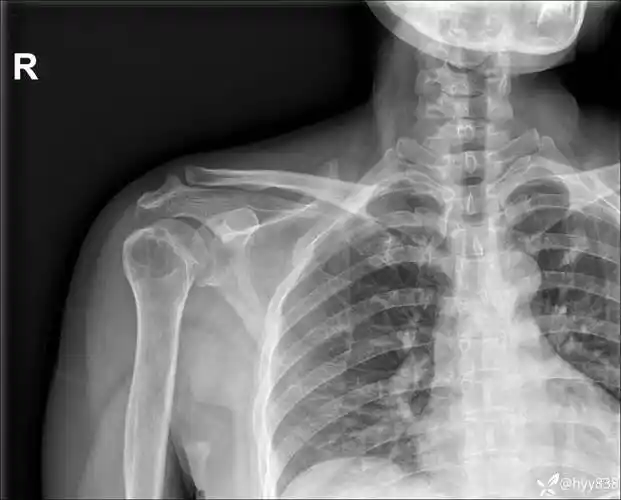

陈旧性肩锁关节脱位

常规肩锁关节脱位锁骨钩没啥技巧